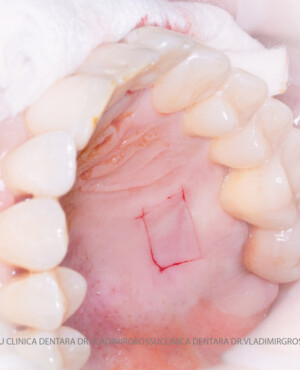

Adiția de gingie (gingivoplastia)

Aditia gingivală este o procedură chirurgicală ce corectează diverse probleme estetice și funcționale, cum ar fi recesiunea gingivală. În implantologia modernă, aditia de țesut moale este utilizată aproape în fiecare intervenție de inserție a implantului dentar pentru a asigura un aspect estetic natural și o bună integrare a implantului în cavitatea bucală.